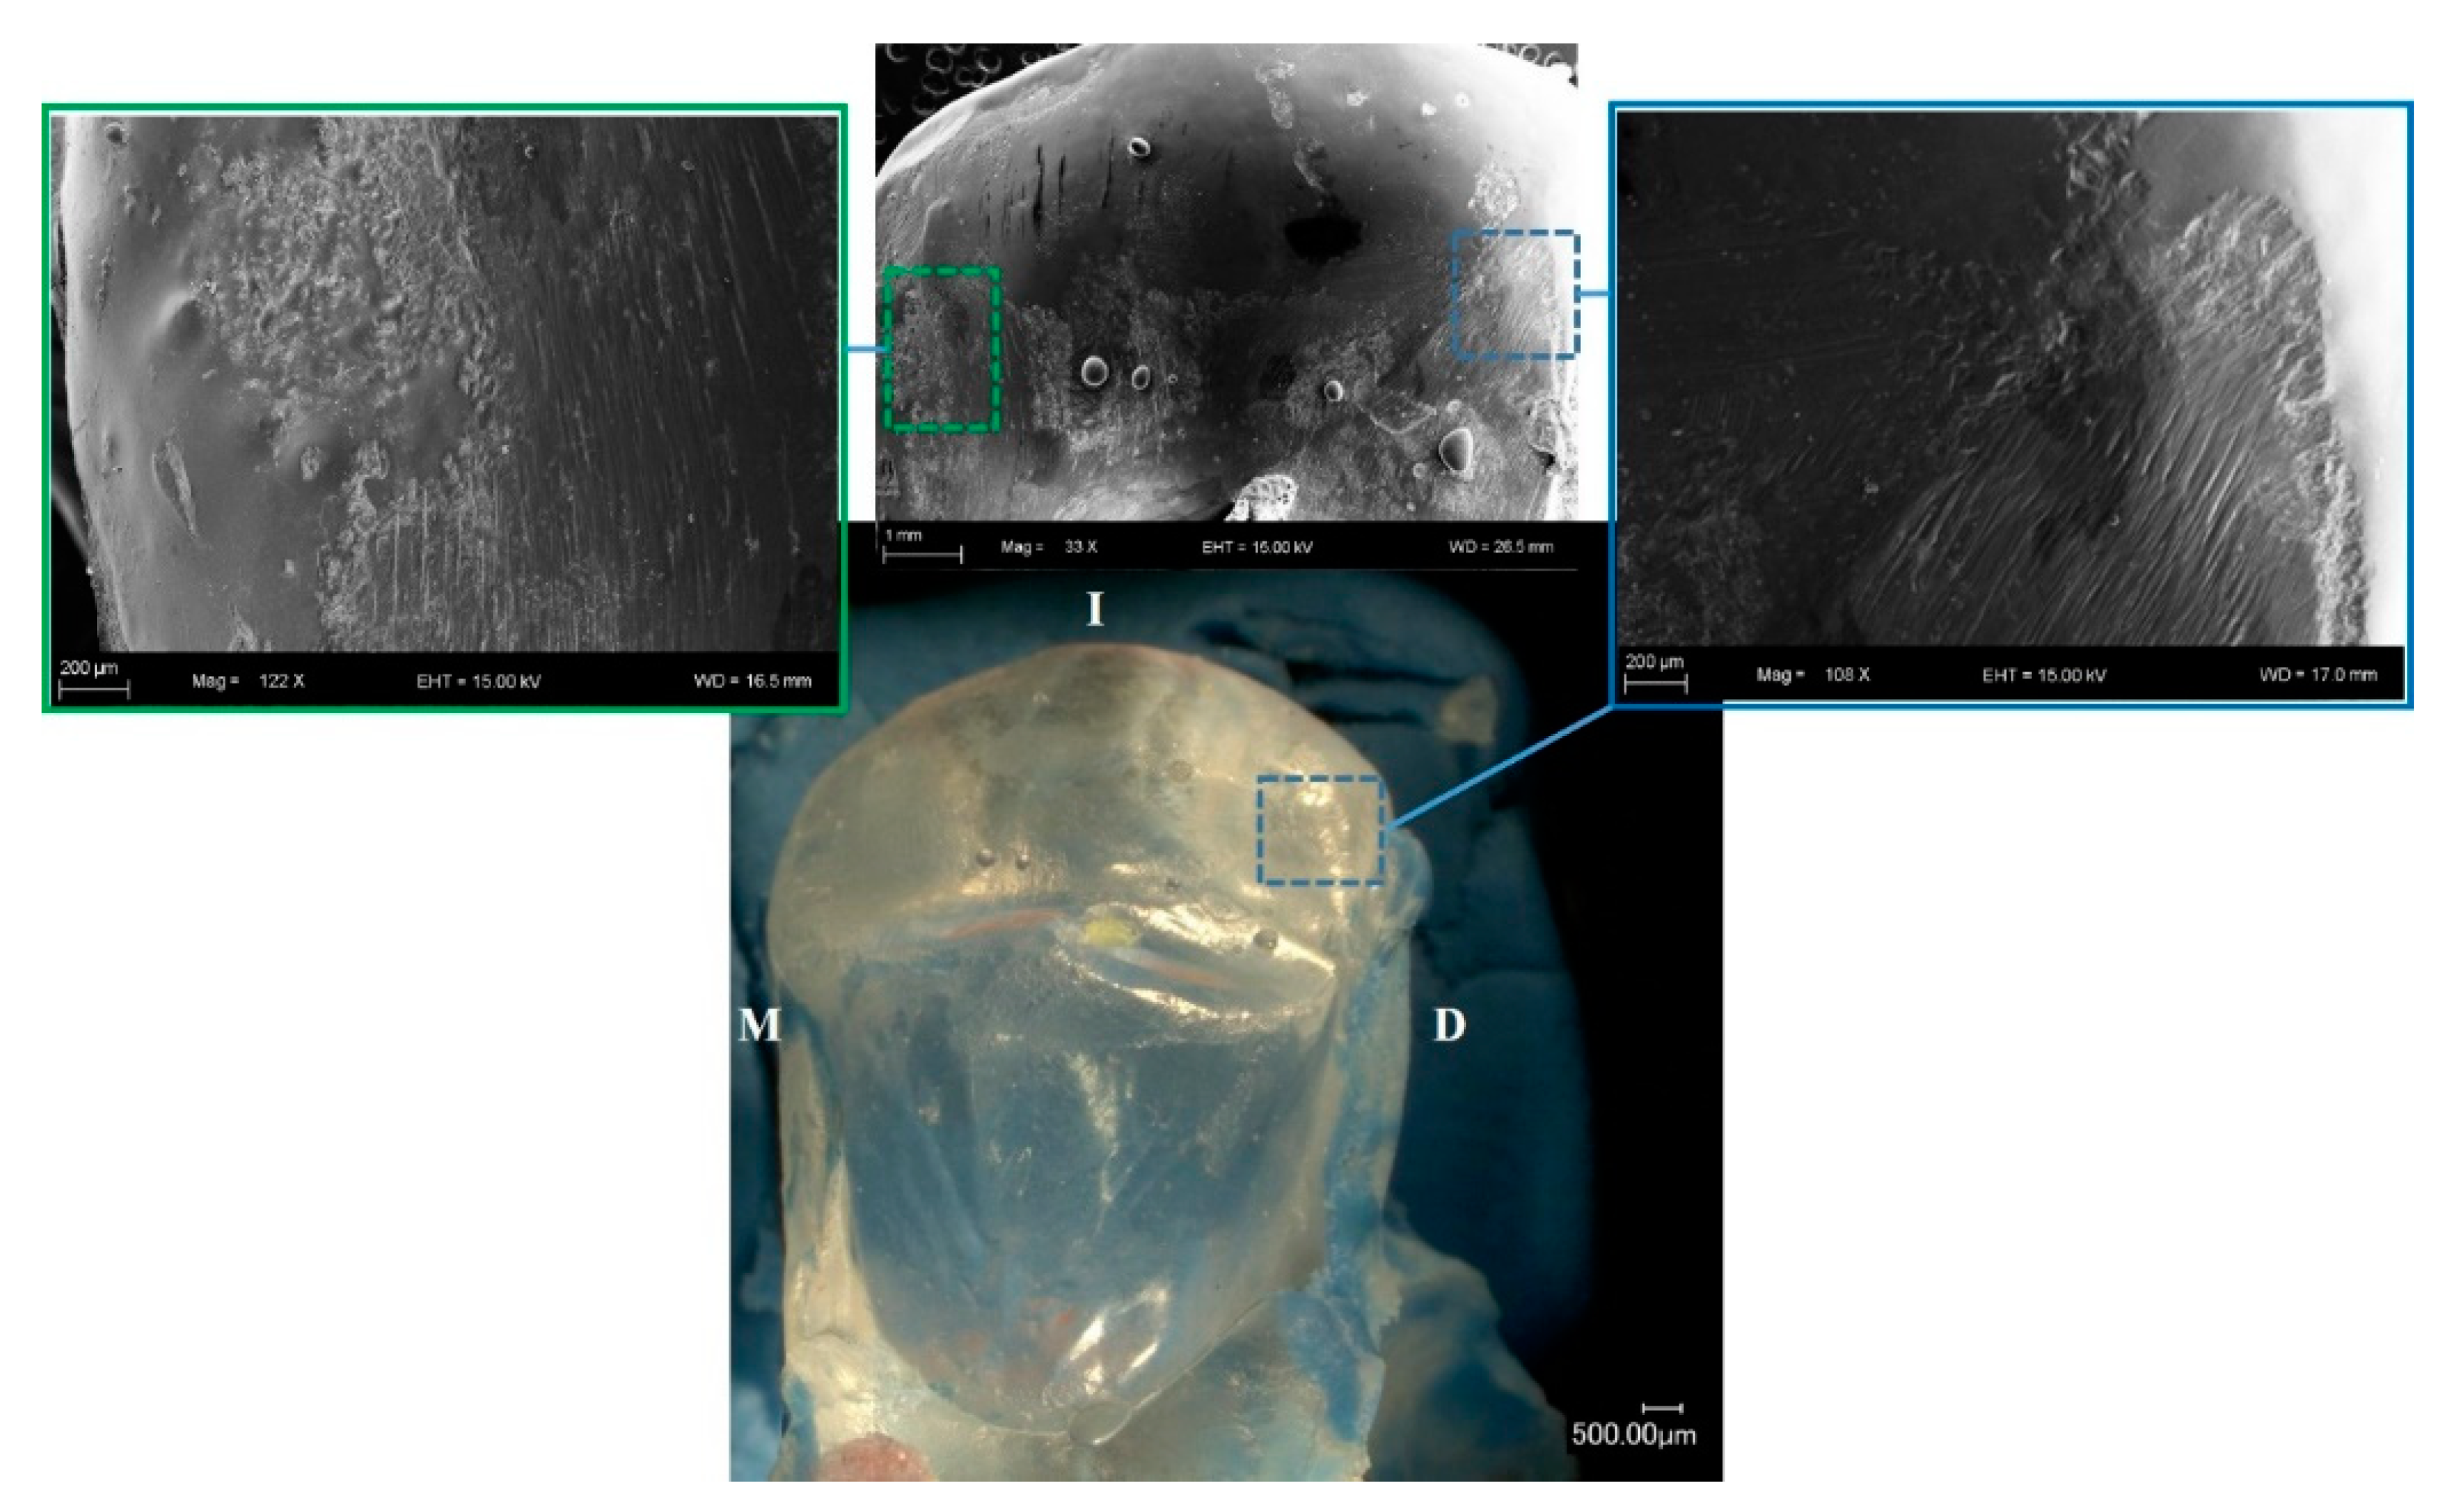

3.1. Topography Analysis